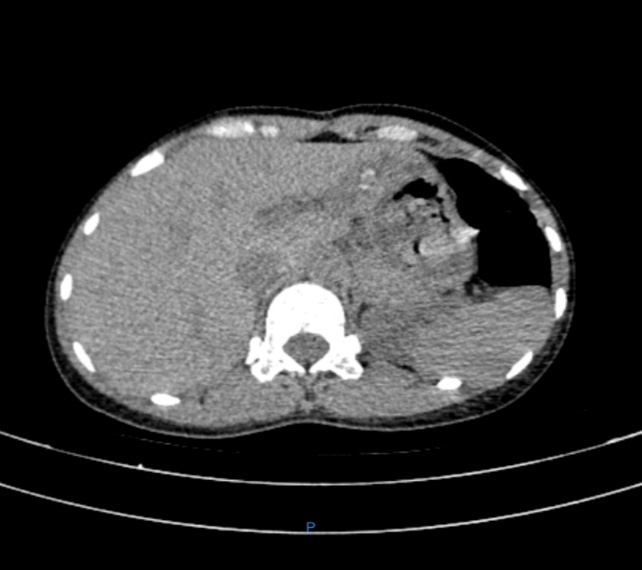

Bệnh nhân nữ 67 tuổi xuất hiện đau hạ sườn phải từng đợt nhiều năm, Mỗi lần đau thường kèm theo sốt, vàng da. BN đã đi khám ở tuyến trên được chẩn đoán tắc mật do sỏi ống mật chủ và sỏi trên gan. BN được chỉ phẫu thuật và quyết định mổ tại BVĐK Hải Dương. Chúng tôi sau khi xem xét hồ sơ bệnh án đã quyết định thực hiện phẫu thuật nội soi tán sỏi OMC và sỏi trên gan kèm tán sỏi Laser. Ca mổ đã diễn ra vô cùng thuận lợi. Sau 2 tiếng ca mổ đã hoàn thành. Sỏi trên gan và sỏi OMC được tán nhỏ và lấy qua nội soi. Sau 10 ngày điều trị hậu phẫu bệnh nhân đã được ra viện.

Hình ảnh sỏi và BN sau mổ với vết mổ rất nhỏ